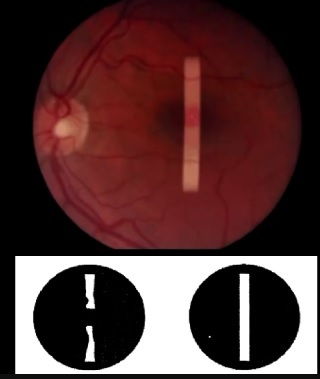

O que é o Sinal de Watzke-Allen?

Visualização de uma Faixa de Luz com uma interrupção no meio, pelo paciente com BM, quando iluminamos a região macular com uma iluminação em fenda.